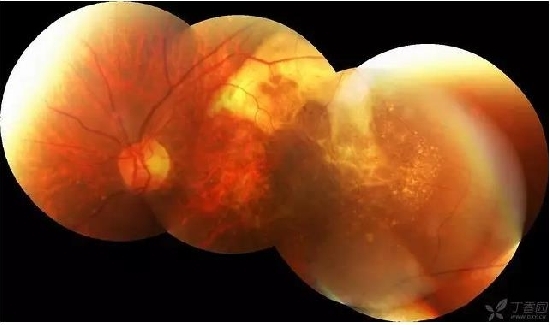

患者,女,48岁,突发左眼视力下降3天,素健,查体:VOD 0.6 VOS HM 出血下方可见橘黄色病灶。考虑PCV,因为出血太大,没敢看,让她去省里了。后面就失访了。请教这个病人pcv是否正确?该如何处理,止血还是活血?OCT上是指样征么?

患者,女,74岁。左眼视物模糊3个月。高血压病史。。查体:VOD 0.6 VOS HM 右眼黄斑玻璃膜疣,左眼大片网膜下出血,造影晚期可见荧光渗漏。还是考虑老黄。当时动员她打针,拒绝。半年后复查,变成瘢痕了,照相是小瞳孔下拍的,所以不全。